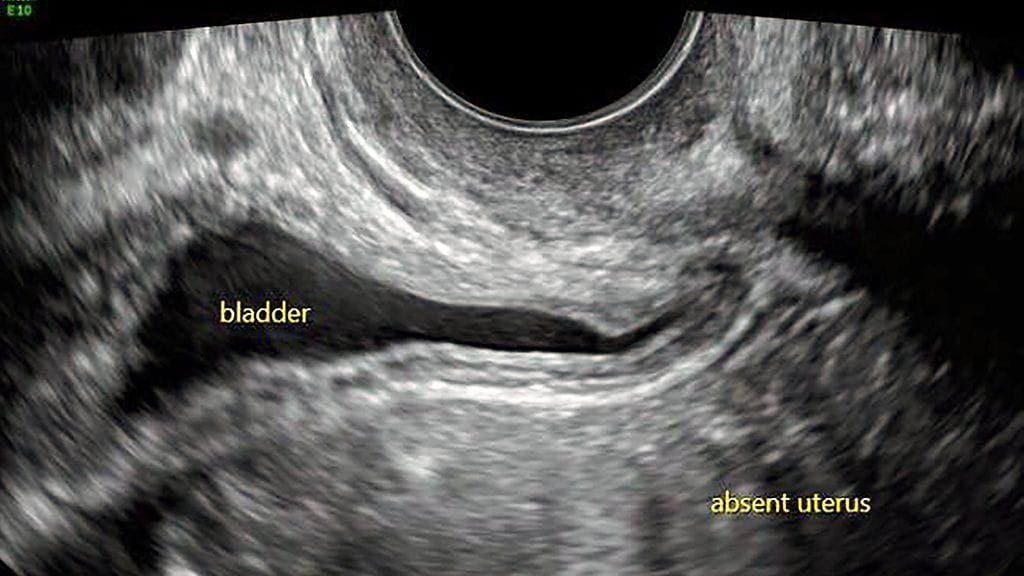

Australialainen Kirstie Coffey sai teini-ikäisenä tietää, ettei hän voisi koskaan synnyttää lasta. Naiselle diagnosoitiin harvinainen Mayer–Rokitansky–Küster–Hauserin oireyhtymä, joka tarkoittaa kohdun synnynnäistä puuttumista. Nainen pystyy tuottamaan munasoluja, mutta kohdun puuttumisen vuoksi raskaus ei ole mahdollinen.